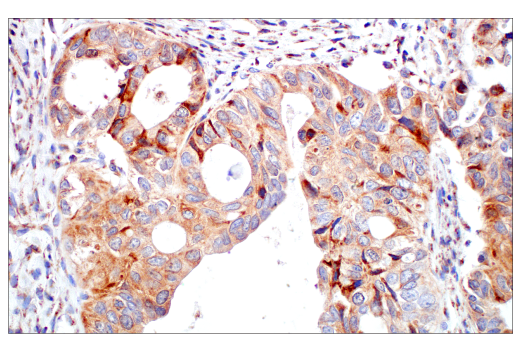

Immunohistochemical analysis of paraffin-embedded human endometrioid adenocarcinoma using DHFR (E6L1H) Rabbit mAb.

Immunohistochemistry Image 2: DHFR (E6L1H) Rabbit Monoclonal Antibody